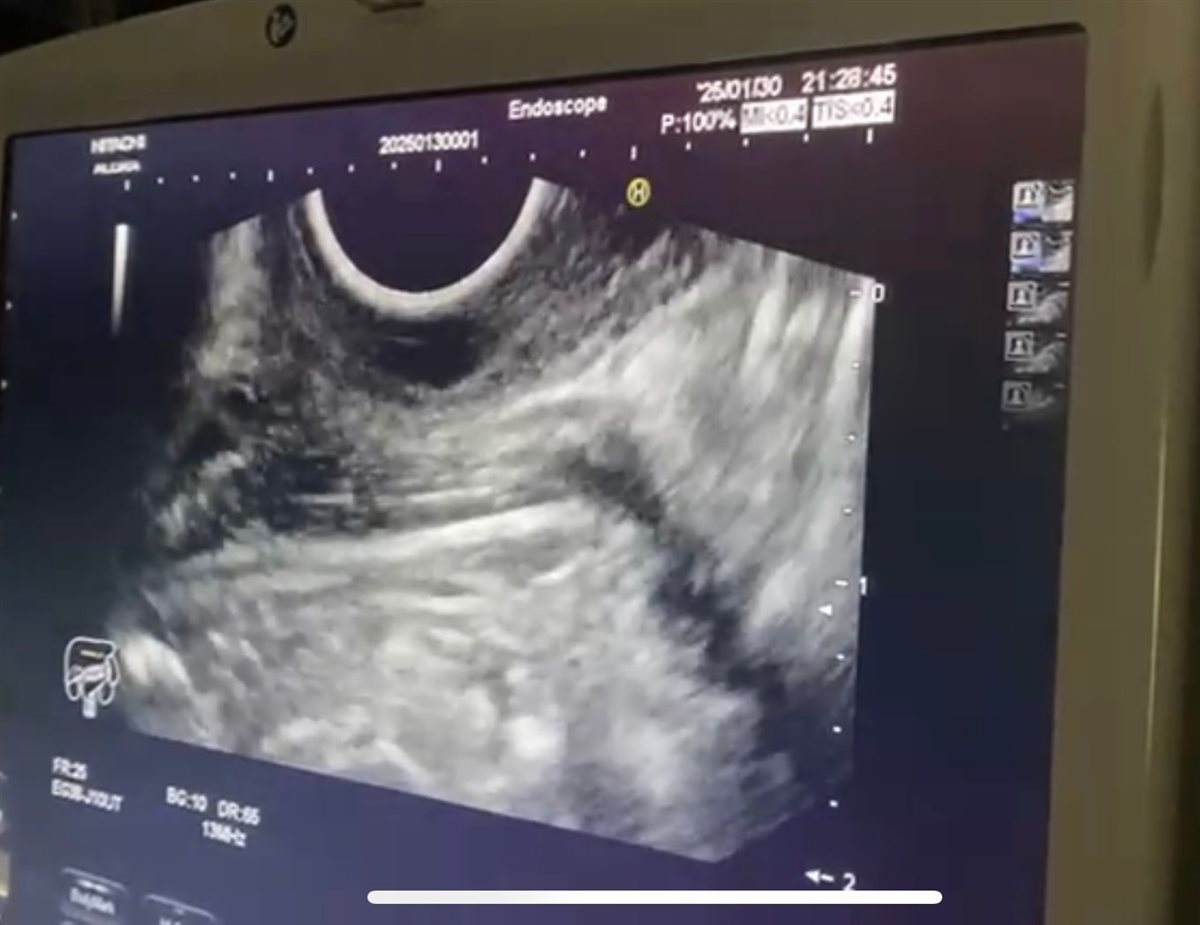

نجحت وحدة المناظير بكلية الطب جامعة حلوان في إجراء أول عملية من نوعها باستخدام منظار الموجات فوق الصوتية لتشخيص واستئصال ورم بالمريء في جلسة واحدة، دون الحاجة لإجراء فتحات جراحية، وذلك بمستشفى بدر الجامعي.

وتمت العملية في غضون 30 دقيقة باستخدام تقنية مناظير الفراغ الثالث، حيث تم تحديد نوع الورم ومكانه وحجمه ومنشئه عبر منظار الموجات فوق الصوتية، ثم استئصاله مباشرة في نفس الجلسة. وتميزت العملية بتوفير الوقت على المريضة وتجنيبها مخاطر التخدير المتكرر، حيث تم خروجها من المستشفى خلال 24 ساعة في حالة صحية ممتازة دون أي مضاعفات.

أجريت العملية تحت إشراف الدكتور شريف البحيري، مدرس الباطنة العامة بكلية الطب واستشاري المناظير التداخلية ومناظير الفراغ الثالث، والذي تلقى تدريبًا متخصصًا على هذه التقنية المتقدمة في جامعة كاتب أتاتورك بتركيا خلال مهمة علمية من جامعة حلوان.